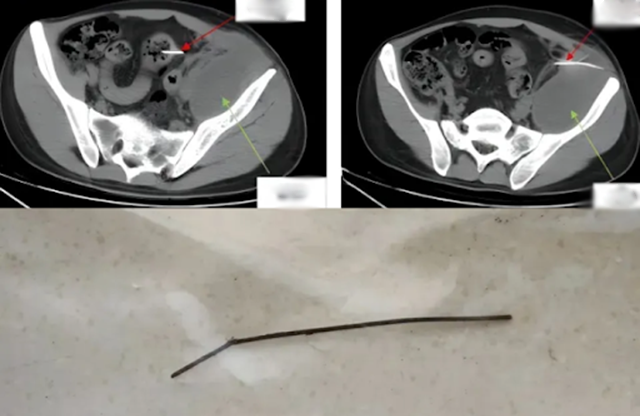

Chàng trai 28 tuổi đau bụng vì nuốt phải dị vật nhọn dài 13cm (Ảnh BV cung cấp)

Tại đây, Phó trưởng khoa Ngoại Tổng hợp Cao Yanbing thực hiện chụp CT bụng cho Tiểu Thiện và phát hiện dị vật lớn đã mắc kẹt lâu ngày, gây viêm nhiễm và thủng ruột. “Dị vật dài 13cm, một đầu nhọn, đã xuyên qua thành ruột, tạo mủ lớn sau phúc mạc. Phẫu thuật là cần thiết ngay lập tức" - bác sĩ Cao cho biết.

Ca phẫu thuật kéo dài 2 giờ 40 phút bằng phương pháp nội soi. Các bác sĩ lấy ra một xiên kim loại dài 13cm, thường dùng để xiên thịt nướng. Chiếc xiên đã xuyên qua đại tràng sigma, vào phúc mạc bên trái, có dấu hiệu rỉ sét. Sau khi lấy dị vật, bác sĩ xử lý áp xe phúc mạc, hố chậu và loại bỏ 180ml mủ hôi thối trước khi khâu lại ruột.